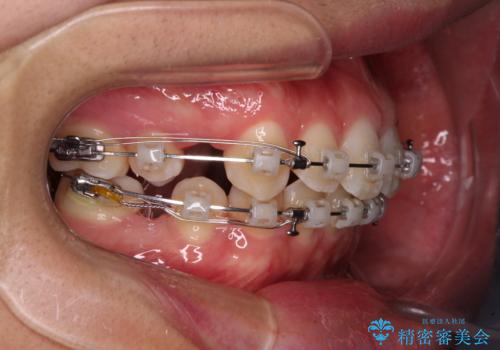

- 矯正装置

- クリアブラケット

- 2年11ヶ月

- 治療回数

- 30回以上

口元を極端に引っ込めた印象にしないため、上顎は左右第一小臼歯2本を、下顎は左右第二小臼歯2本を抜歯し、ワイヤー装置にて矯正治療を行うこととしました。